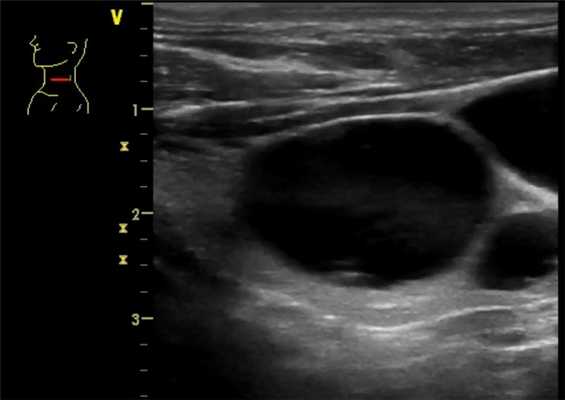

- Обычно однокамерная тонкостенная киста

- Анэхогенное содержимое с задним акустическим усилением

Ультрасонографические данные. Ультразвуковое сканирование в оттенках серого. Однокамерная тонкостенная киста является типичной находкой. У нее имеется тонкая, эхогенная стенка и анэхогенное содержимое с задним акустическим усилением. Характерны эхогенные очаги с артефактами хвоста кометы, представляющие собой взвешенные коллоидные агрегаты. ± коллоидные скопления (нерегулярный, эхогенный, аваскулярный детрит). Если было предыдущее кровоизлияние в кисту, то она будет толстостенной с детритом ± уровень жидкости. Толстые септы ± кометный хвост, если киста возникает из гиперпластического узла. Фон узла сплошной, а кистозные пространства переменных размеров. Узел будет выглядеть солидным, с хорошо выраженными границами, овальным и, изоэхогенным, а внутри не обнаруживается точечной кальцификации. Коллоидные скопления разбросаны в кистозных пространствах